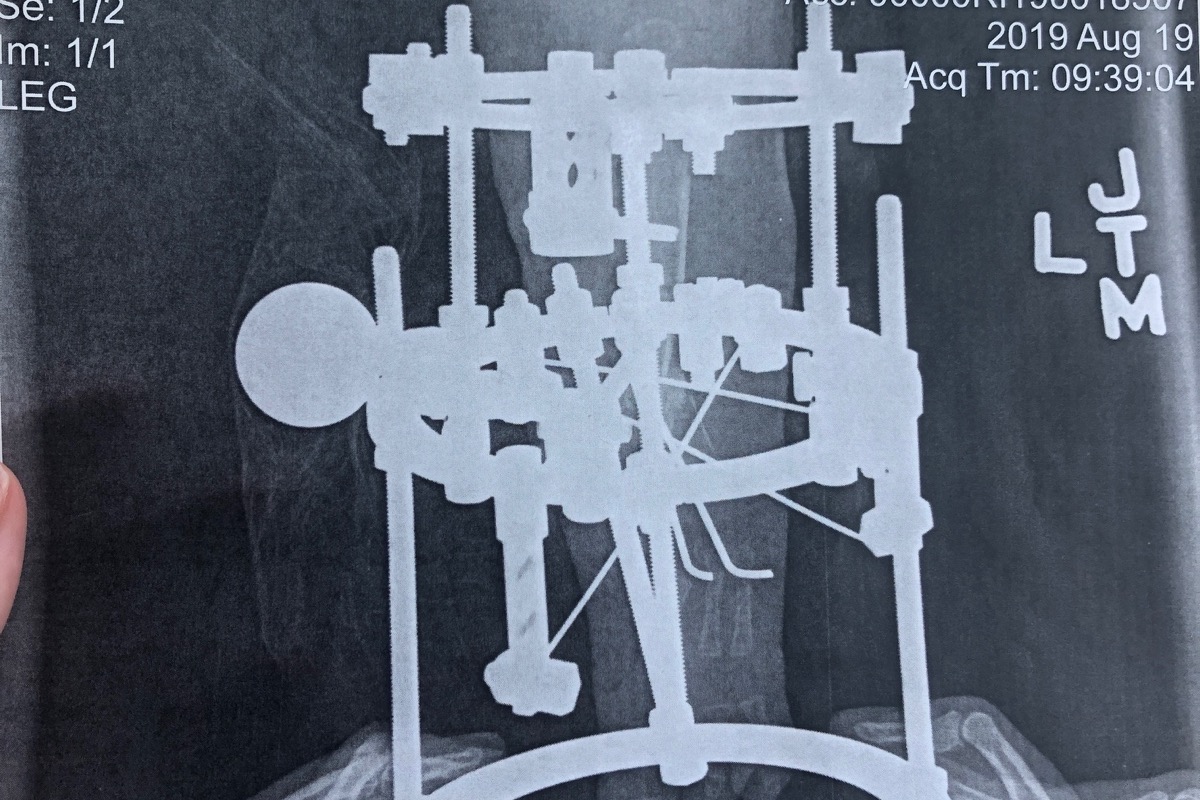

Caylee had her first surgery on August 13th in Baltimore Maryland at Sinai Hospital. She had her tibia corrected and a SUPER ankle procedure that rebuilt her ankle. She still currently has an external fixator on her leg. We had to turn it for 6 weeks slowly pulling her bone apart to fix the bow and to gain some length. She has many pins in her leg. We are now done turning and are in the healing period while we wait for her bone to heal back together. She will have x rays in 2 more weeks and we will find out when it can be removed. Once it’s removed she will get another pin through the bone under a cast to continue healing and will then have to be put under anesthesia again to get that pin removed .